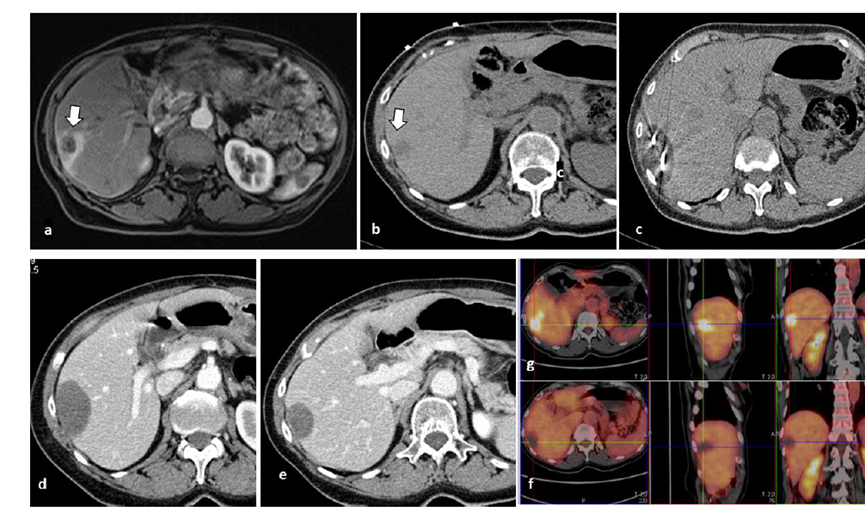

冷冻消融胆囊附近肿瘤病灶

(A)动脉期 MRI 显示胆囊附近有外周增强病变(箭头)。

(B)手术过程中 CT 显示冷冻探针位于病灶内。

(C)消融后,术后 1 个月CT 显示完全消融(箭头)。

(A)动脉期CT图像显示有一个包膜下结节(箭头)。(C) 在手术过程中的CT显示一个冷冻探针位于病灶内。随访时间中位数为7个月(范围:3-12个月),随访期间患者无局部肿瘤进展或死亡。

(A)门静脉期 CT 图像显示胆囊附近有病变(箭头)。(D)消融手术后 1 个月CT 显示完全消融。

79 岁男性,肝转移(结直肠癌)肿瘤的完全消融病例

( a ) 轴向 MRI 和 ( b ) 轴向 CT 显示肝S8段有一个16mm的病灶,邻近肝缘。( c )冷冻消融期间CT显示放置了2个冷冻探针,低密度冰球包围病灶。(d)术后1个月随访 CT显示冰球对应的坏死区域,未见复发。(f)与基线影像(g)相比,12个月后的FDG-PET/CT显示未见FDG摄取。

(a)轴向CT显示病变位置毗邻心脏和上腔静脉(黑色箭头)。1个月后的轴向(e)和冠状位(f)增强CT扫描显示低密度区域,由于肉芽组织反应引起的边缘增强。